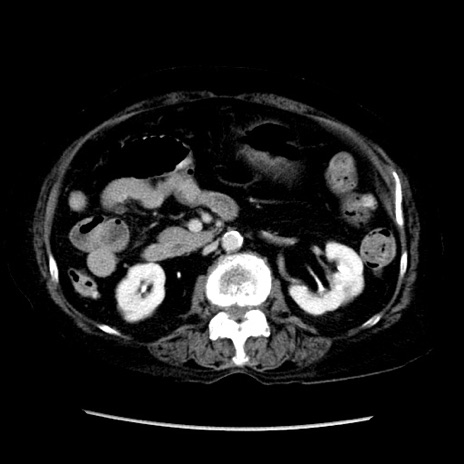

症例14(横断像)

【症例】 90歳代女性

【主訴】 腹痛・嘔吐

【現病歴】今朝から左側腹部痛を認めた。 経過観察していたが、嘔吐を認めたため来院。

【既往歴】 子宮癌術後

【身体所見】 意識清明、BP 127/54mmHg、P 98bpm Sp02 95%(RA)、BT 35.8°C、腹部平坦・軟腸ぜん動音聴取良好、右下腹部圧痛(+) 反跳痛なし

【データ】WBC 9800、CRP 0.46